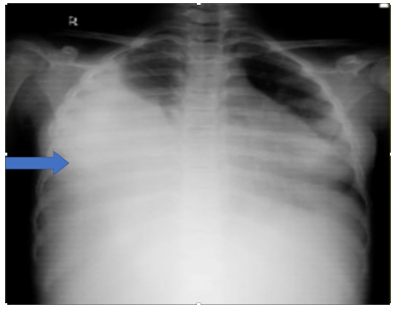

Diagnostic Assessment: Her hematological parameters were within limits except thrombocytosis. Serum biochemistry was normal. Liver and kidney function tests were within limits.  Urine analysis was also normal. Therapeutic thoracocentesis was done and around 750ml of pleural fluid was aspirated gradually over the course of 48 hours following which she improved symptomatically. Pleural fluid analysis revealed a blood stained, sterile fluid, with protein content of 4.4 gm/dL, glucose of 91mg/dl, and LDH of 1043 IU/L. Fluid cytology revealed markedly increased lymphoid cell with plenty of RBCs. No malignant cells were visualized. Chest radiograph was suggestive of a massive right sided pleural effusion (Fig 1).

Figure 1: Chest x-ray showing right sided massive pleural effusion with mediastinal shift towards left.